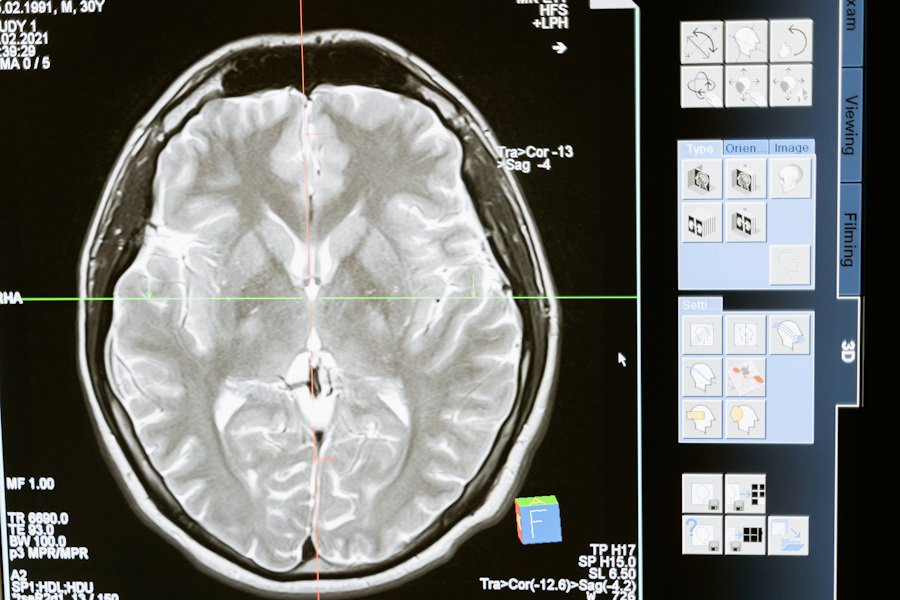

Интернациональная группа учёных, проведя масштабное исследование, выявила пять моделей старения мозга у человека. В своей публикации на портале Nature Medicine, ученые проанализировали тысячи сканов МРТ с помощью машинного обучения, чтобы понять, как старение влияет на мозг.

Процесс старения мозга зависит от множества факторов, включая образ жизни, генетику и различные заболевания, связанные с возрастом. Магнитно-резонансная томография (МРТ) и искусственный интеллект помогли исследователям выявить нейроанатомические изменения, происходящие с возрастом. Проще говоря, ИИ помог ученым понять, какие именно части мозга страдают больше всего и как это связано с рисками для здоровья.